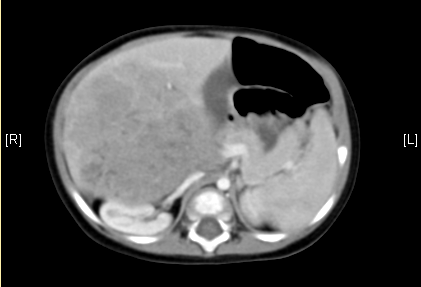

上腹部增强CT:考虑肝母细胞瘤可能性大。

术前CT检查:动脉期

静脉期

平衡期